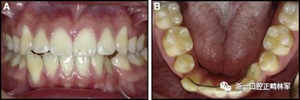

臨床檢查顯示固定保持器完好,弓絲沒有斷裂(圖13)。在下頜右側(cè)中切牙唇側(cè)和鄰近側(cè)切牙的舌側(cè)注意到有牙齦退縮。這些牙齒在退縮方向上存在顯著的扭矩差異。下頜的左側(cè)尖牙頰側(cè)錯(cuò)位,而右側(cè)尖牙舌側(cè)傾斜。三維射線照片證實(shí)了下頜右側(cè)尖牙面?zhèn)妊啦酃菃适?,右?cè)中切牙的喪失程度較輕。右側(cè)側(cè)切牙根也從舌側(cè)骨面上扭轉(zhuǎn)出來(圖14)。

圖13.粘合到尖牙和切牙上的柔性螺旋弓絲保持器,伴有牙齦退縮和附著喪失,中切牙之間嚴(yán)重的扭矩差異以及兩顆尖牙的橫向移動和扭矩。牙周問題和牙齒移動的嚴(yán)重程度均為牙周正畸聯(lián)合治療的指征:A,正面視圖; B,咬合面視圖。